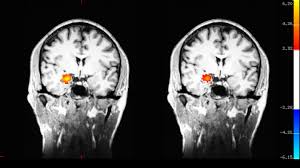

Bottom line: mindfulness practice is training for our minds and emotions that can change the way our brains operate.

Personally, I have experienced many of the benefits listed above and feel incredibly grateful to have had the opportunity and resources to access this practice. As Canadian neurologist Donald Hebb once said, “what fires together wires together.” The more we react, think, attend, converse, etc. a certain way, the more likely we are to do it again. Like most humans, I can be so easily controlled by my conditioning, but slowing down to pay attention to my inner experience is incredibly helpful. As Victor Frankl said,